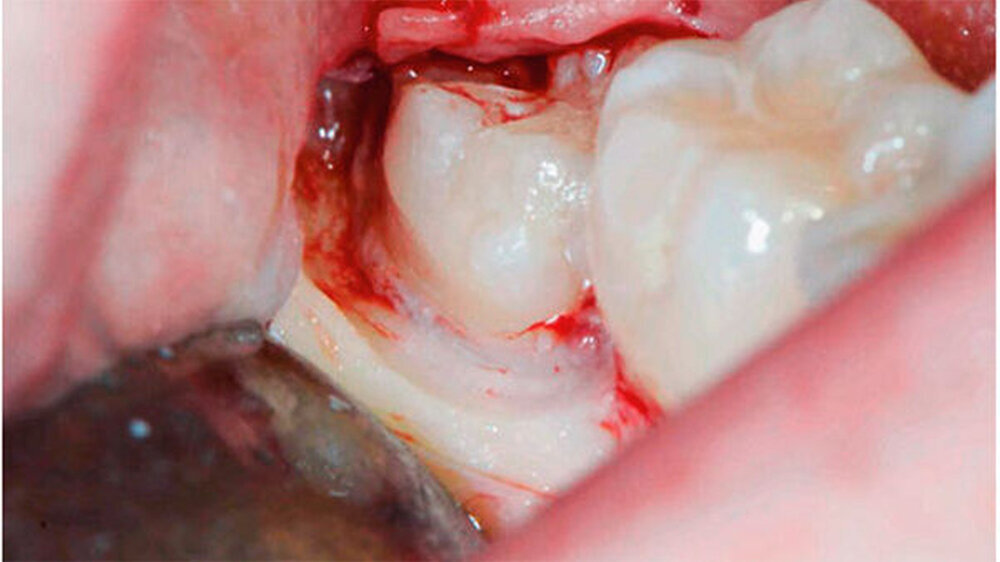

Bei der 27-jährigen, gesunden Patientin, kam es zu rezidivierender Perikoronitis des teilretinierten Zahns 48 (Abb. 1a). Primär wurde eine OPT-Aufnahme zur Operationsplanung erstellt (Abb. 1b). Dabei zeigte sich eine komplette Überlagerung der Zahnwurzel über den C. mandibulae. Zur weiteren Abklärung der Lagebeziehung wurde eine DVT-Aufnahme erstellt (Abb. 1c). Eine linguale Lage des C. mandibulae zur Zahnwurzel konnte festgestellt werden. Eine knöcherne Begrenzung des C. mandibulae zur Zahnwurzel fehlte.

Aufgrund des hohen intraoperativen Läsionsrisikos für den N. alveolaris inferior wurde eine Koronektomie geplant; die Patientin willigte nach eingehender Aufklärung ein. Präoperativ spülte sie mit 0,2 Prozent Chlorhexidin-Mundspülung (Curasept ADS® 220, Curaden AG, Kriens, Schweiz). Eine Leitungsanästhesie des N. alveolaris inferior sowie eine Infiltrationsanästhesie bukkal wurden durchgeführt (Ultracain ds forte, Sanofi-Aventis AG, Vernier, Schweiz).

Die Koronektomie wurde, wie in Abbildungen 1a bis k gezeigt, durchgeführt. Die Schnittführung erfolgte intrasulkulär beim Nachbarzahn mit kurzer disto-bukkaler Entlastung über dem Ramus ascendens. Anschließend wurde ein bukkaler Mukoperiostlappen gebildet. Die Zahnkrone, welche von Knochen bedeckt war, wurde mit dem Handstück und dem Rosenbohrer unter ständiger NaCl-Kühlung bis zur Schmelz-Zement-Grenze freigelegt.

Anschließend wurde mit einem Fissurenbohrer die Krone an der Schmelz-Zement-Grenze abgetrennt. Es wird empfohlen, den Fissurenbohrer nur so weit in den Zahn vordringen zu lassen, dass die lingualen Weichgewebe nicht verletzt werden.

Danach wurde die Krone mit dem Hebel abgetrennt. Dabei ist darauf zu achten, dass die Wurzel nicht anluxiert wird. Falls der Wurzelblock nach dem Dekapitieren eine verstärkte Mobilität aufweisen sollte, muss aufgrund einer erhöhten Infektionsgefahr eine komplette Extraktion durchgeführt werden.

Sobald die Krone abgelöst war, konnte mit einem Rosenbohrer unter ständigem Schutz der lingualen Weichgewebe mittels Raspatorium verbleibender Schmelz abgetragen werden. Der Wurzelblock sollte einige Millimeter unterhalb der bukkalen Knochenkante abgetragen werden. Anschließend wurden scharfe Zahn- und Knochenkanten geglättet. Die Pulpa bedarf keiner weiteren Behandlung.

Nach Kürettage und Spülung mit NaCl-Lösung wurde der Lappen reponiert und ein primärer Wundverschluss durchgeführt (Supramid 4–0, B Braun Medical AG, Sempach, Schweiz). Zur Analgesie wurde der Patientin Mefenaminsäure 500 mg (Mefenacid, Streuli Pharma AG, Uznach, Schweiz) dreimal täglich verordnet.